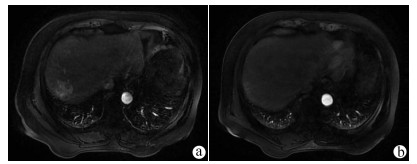

A case of primary hepatic neuroendocrine tumor

LING JK, WANG M, YUAN J, et al. CT and MRI findings of primary hepatic neuroendocrine neoplasm[J]. Chin J Oncol, 2017, 39(8): 600-606. DOI: 10.3760/cma.j.issn.0253-3766.2017.08.008.

李家开, 王敏, 袁静, 等. 肝脏原发性神经内分泌肿瘤的CT和磁共振成像表现[J]. 中华肿瘤杂志, 2017, 39(8): 600-606. DOI: 10.3760/cma.j.issn.0253-3766.2017.08.008.